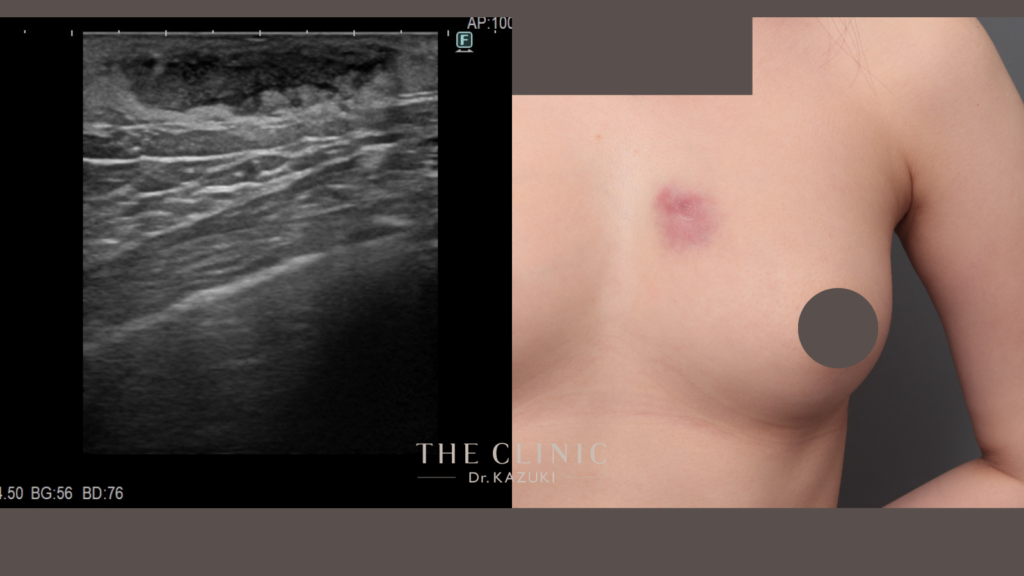

少量の脂肪吸引にも関わらず、片側に3か所の傷がつけられ、創縁を愛護的に扱っていなかったため、瘢痕がしっかりと残っています。通常は、脚の付け根(ビキニライン)にポート創部を置き、創縁を愛護的に扱い、

目立つ瘢痕がつかないようにします。